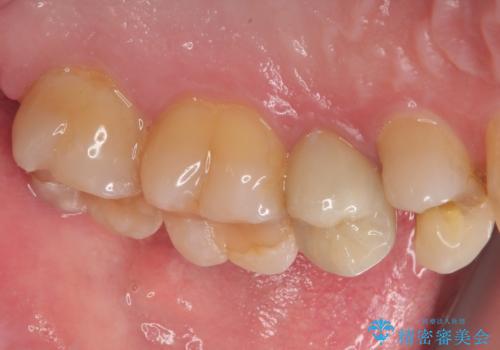

- 左上に違和感があるとのことで来院された患者様です。レントゲン撮影の結果左上の6番目の歯の近心側に虫歯を認め、フロスも引っかかる状態でしたのでセラミックインレーにて修復治療を行っていくこととしました。

拡大鏡視野下でコンポジットレジン、虫歯を除去しセラミックインレーに適した形に整えました。